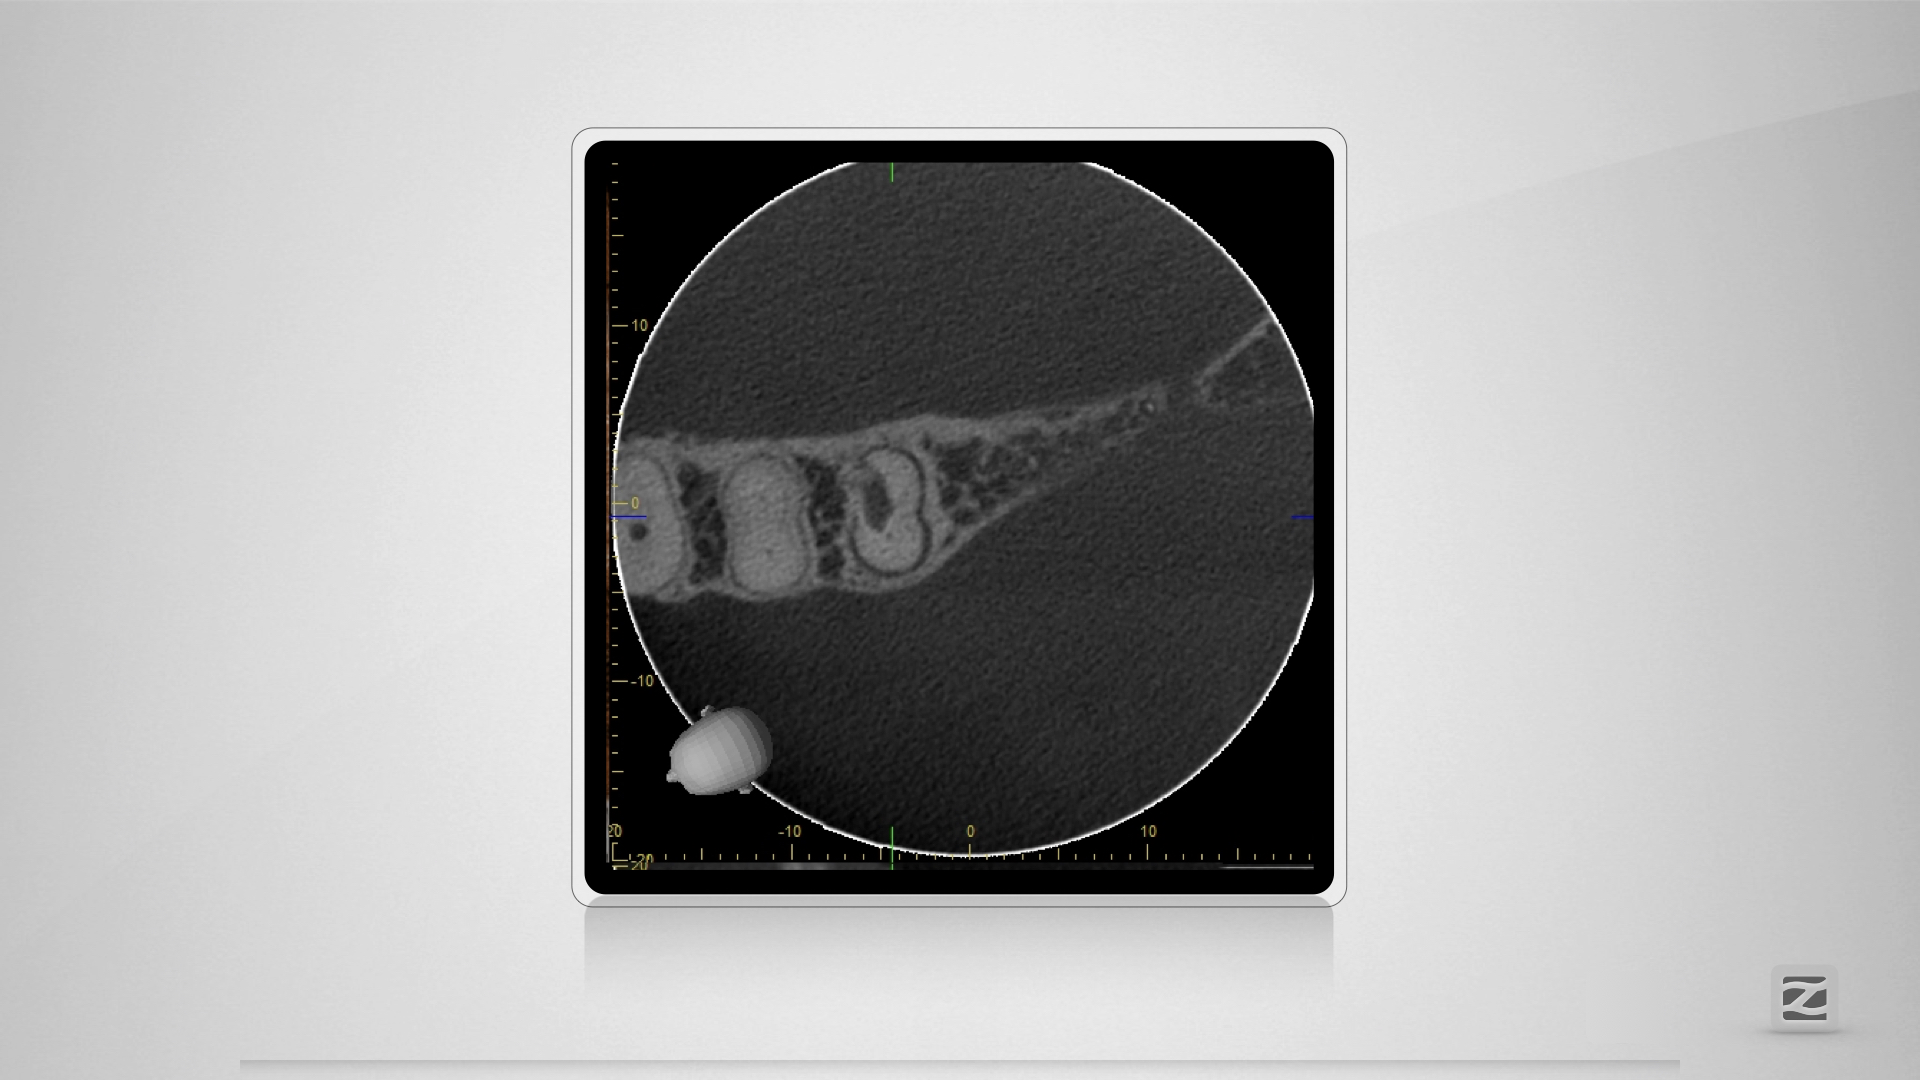

PerforationD.006

Übermut tut selten gut.